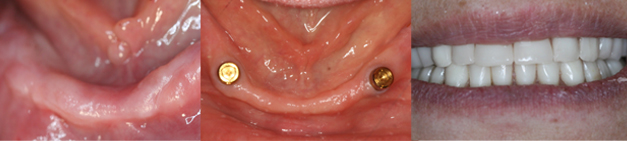

IMPLANT PLACEMENT

Card image Card image Card image Card image Card image Actual Practice Photographs ©Dr.Pavan Bopanna